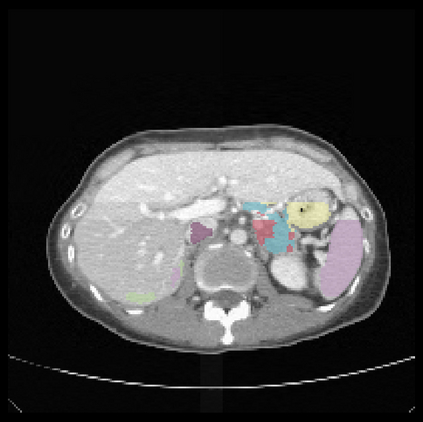

It is imperative to ensure the robustness of deep learning models in critical applications such as, healthcare. While recent advances in deep learning have improved the performance of volumetric medical image segmentation models, these models cannot be deployed for real-world applications immediately due to their vulnerability to adversarial attacks. We present a 3D frequency domain adversarial attack for volumetric medical image segmentation models and demonstrate its advantages over conventional input or voxel domain attacks. Using our proposed attack, we introduce a novel frequency domain adversarial training approach for optimizing a robust model against voxel and frequency domain attacks. Moreover, we propose frequency consistency loss to regulate our frequency domain adversarial training that achieves a better tradeoff between model's performance on clean and adversarial samples. Code is publicly available at https://github.com/asif-hanif/vafa.